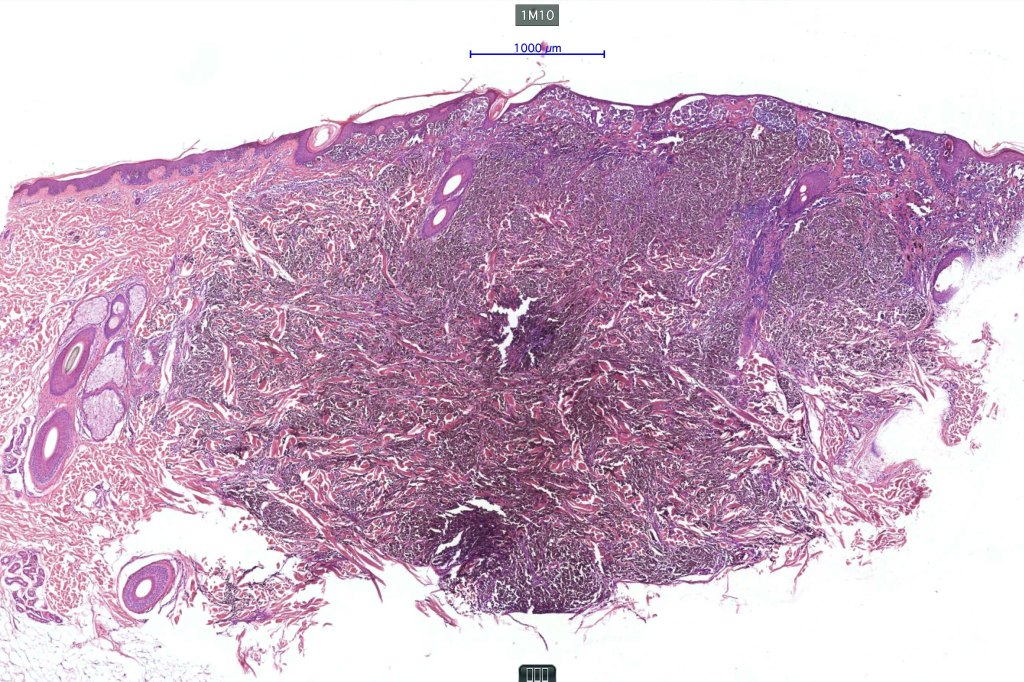

1.typical melanoma in the superficial aspect overlying a deep penetrating nevus-like deeper component

2. typical epithelioid melanoma in the superficial aspect associated with very marked perivascular and appendageal spread giving rise to a plexiform appearance

3. a deep penetrating nevus like lesion showing obvious signs of malignancy including greater pleomorphism than is usually seen combined with excessive mitotic activity, deep mitoses and atypical forms

4. melanoma which shows a deep penetrating architecture although the cytology remains epithelioid throughout